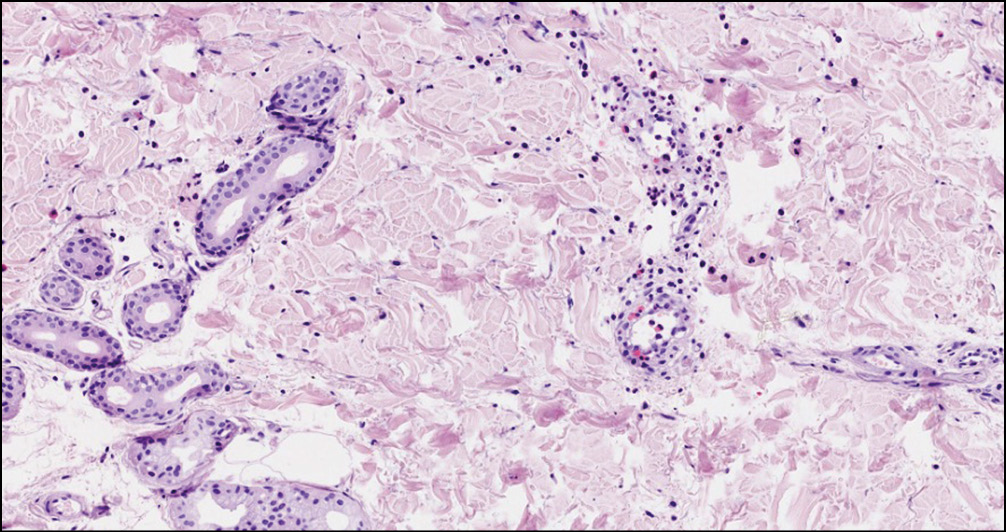

13.11.2019 с целью исключения УВ в условиях стационара была выполнена биопсия кожи (рисунок).

Рис. Окрашенный срез биопсии кожи. Эпидермис обычной толщины, его слои дифференцированы, слабый рыхлый кератоз. Стенки сосудов сосочкового и сетчатого слоёв дермы утолщены за счёт отёка и набухания эндотелиоцитов. Вокруг сосудов слабая инфильтрация из гистиоцитов, лимфоцитов, эозинофильных гранулоцитов. Местами единичные эозинофильные лейкоциты проникают в сосудистую стенку. Количество эозинофилов ― от 7 до 12 в поле зрения при увеличении в 400 раз. Изменения соответствуют уртикарному васкулиту.

Fig. Stained skin biopsy section. The epidermis is of normal thickness, its layers are differentiated, weak loose keratosis. The walls of the vessels of the papillary and reticular layers of the dermis are thickened due to edema and swelling of endothelial cells. Around the vessels there is weak infiltration from histiocytes, lymphocytes, eosinophilic granulocytes. In places, single eosinophilic leukocytes penetrate the vascular wall. The number of eosinophils is from 7 to 12 in the field of view with a magnification of 400 times. The changes correspond to urticarial vasculitis.